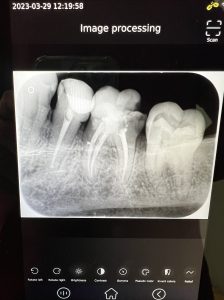

1.Diagnóstico: se realizan preguntas guiadas por parte del dentista, durante las cuales el paciente informa de cómo es el dolor qué siente, dónde se localiza, con qué intensidad lo nota, si puede calmarse aplicando frío, etc, todo encaminado a hacer un buen diagnóstico. Además, se realizan radiografías para verificar el estado del diente y su anatomía (longitud de las raíces y estado de las mismas).

6. Control: se realiza un control y una radiografía 1 semana después de terminado el tratamiento para evaluar que el diente se encuentra sin dolor y en perfecto estado para recibir el alta.

- Radiografías Digitales HD